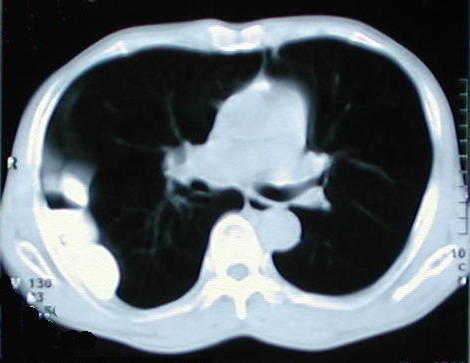

Tomografía Computarizada

Tomografía de ½ inferior del tórax y abdomen superior con contraste oral, se aprecia desplazamiento del colon hacia la base pulmonar derecha, el campo pulmonar en su periferia y en región subfrénica que comprime y deforma el contorno anterior hepático, también hay contenido de asas delgadas en el tórax.

Corte tomografico del Torax a nivel de la carina bronquial

Corte tomografico del Torax a nivel del tercio inferior del Tórax

Corte tomografico del Torax a nivel inferior de la carina bronquial

Corte tomografico del Torax a nivel de la base del torax